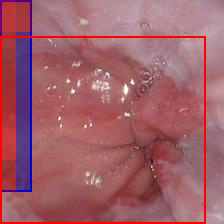

Kvasir Gastrointestinal Disease Detection Dataset – Part of the Kvasir dataset [19], we utilize the Z-line subcategory, where the task is to distinguish between a healthy Z-line and esophagitis at the junction between the esophagus and stomach.

Using the trained models with state-of-the-art performance, we follow the protocol detailed in Section 2.4 and present experimental results on interpretability in Figure 3, Figure 4, and Table 3. In particular, Figure 3 illustrates several qualitative examples, while Table 3 displays pointing game accuracy and mean IoU scores. Finally, Figure 4 represents IoU distributions represented in the form of boxplots. Based on these results, we make the observations below.

Qualitative results can be misleading. In Figure 3, we present qualitative interpretability outputs for all methods considered. As can be seen, depending on the selected subset of images and the method, both accurate and inaccurate interpretability maps can be found. These findings emphasize the danger of making strong claims about interpretability methods based solely on qualitative results, including attention maps.

| Kvasir | Random | 0.88 | 0.98 | 0.72 | 0.54 | 0.36 | 0.34 |

| Supervised | 0.80 | 0.88 | 0.92 | 0.44 | 0.59 | 0.61 | |

| DINO | 0.72 | 0.96 | 0.90 | 0.32 | 0.43 | 0.48 | |

| MAE | 0.52 | 0.82 | 0.80 | 0.52 | 0.59 | 0.62 | |

Attention maps show promise for interpretability. As shown in Table 3 and Figure 4, interpretability results of attention maps and the Chefer method are comparable. Attention maps generally perform better in the pointing game, while the Chefer method yields better IoU results. These observations hold true for the majority of models across all datasets, with the exception of CP-Child, where the Chefer method outperforms attention maps in the pointing game. Based on these findings, we suggest that researchers employ attention maps when the goal is to identify the most important location in an image. In other scenarios, however, we recommend using the Chefer method. In summary, while attention maps show promise, we find that the Chefer method is a more appropriate choice for interpretability in medical datasets.

Bounding box annotations may be inadequate for interpretability evaluation on medical datasets. In this work, we worked with expert clinicians to highlight disease-positive regions with a bounding box to evaluate the efficacy of interpretability maps. However, we discover that this approach comes with significant shortcomings. For instance, in the MURA and Kvasir datasets, regions of interest often occupy large spaces, resulting in annotation boxes that include non-target areas, and leading to inflated results regardless of the method’s actual precision. Therefore, using segmentation maps, which provide detailed pixel-level annotations of the areas of interest, could offer a more precise evaluation in future research.